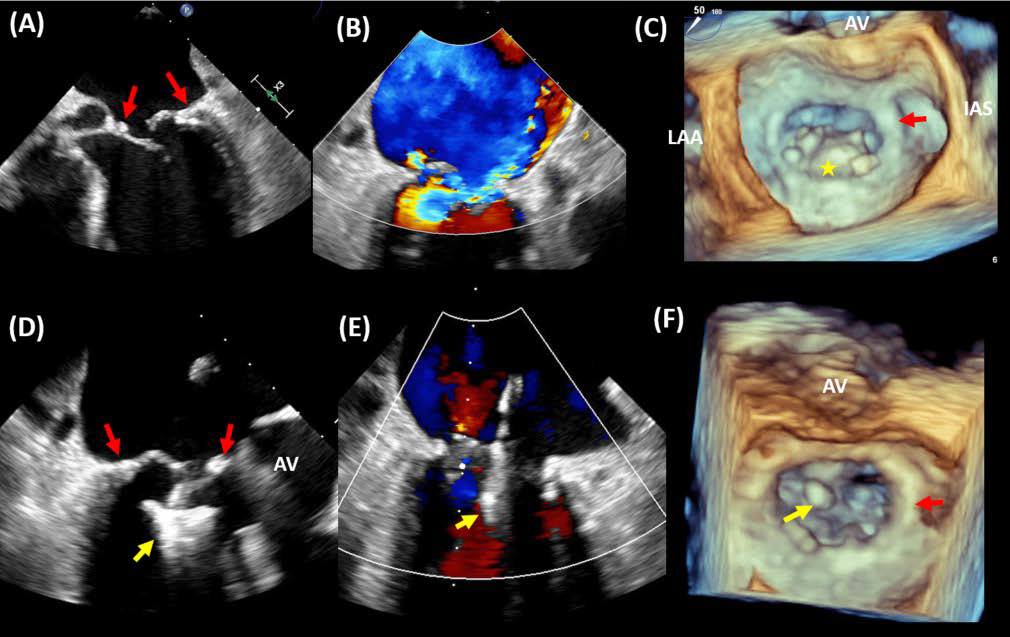

This has led to the rational of TEER in ring. Emerging data has shown this approach to be a feasible option to treat post annuloplasty MR recurrence [81, 82, 83, 84]. There are however some technical considerations that pose challenges in this cohort of patients. First, the leaflet resection performed at the time of surgery may leave insufficient posterior leaflet length for a secure and stable grasp. A MitraClip NT device may be the device of choice in such situations, where grasping of 6 mm of leaflet length may be the only feasible option after surgery. Some reports have demonstrated an alternative technique of grasping the anterior leaflet with the posterior aspect of the annuloplasty ring when sufficient tissue length hinders leaflet grasping as a viable option [85]. Second, the mitral valve area after surgery may be small resulting in elevated diastolic gradients and significant mitral stenosis if a device is implanted. The last challenge to TEER in ring is embedded in the ability to obtain high resolution images appropriate for leaflet visualization and grasping. Standard mitral views may be difficult in the presence of acoustic shadowing that is likely to be present with a mitral annuloplasty ring. Some suggested approaches include off-axis imaging and the use of X-plane imaging frequently to overcome areas of shadowing. The use of 3D imaging for orientation and of clip descent is also key in ensuring successful grasp with minimal manipulation. If TEE proves to be challenging despite all the above, intracardiac echocardiography may be an alternative tool for guidance [86]. Some of the important parameters to obtain in a patient post mitral annuloplasty include mitral valve area, mead diastolic gradient, posterior leaflet length and detailed 2D and 3D imaging of both residual free edges at the site of propsed grasp. Fig. 7 demonstrates recurrent MR post mitral annuloplasty with successful Mitra Clip in ring implantation.

Fig. 7.MitraClip in annuloplasty ring. A case of transcatheter edge-to-edge repair (TEER) in a patient with a surgical mitral valve ring (MVr). (A) Transesophageal echocardiography (TEE) showing a prolapsed posterior leaflet within the MVr (red arrow) resulting in severe eccentric MR (B). 3D TEE imaging demonstrating prolapsed posterior leaflet (*) within the MVr (C). The patient underwent TEER with MitraClip device (yellow arrow) implantation at A2-P2 (D) resulting in mild residual MR (E). 3D TEE imaging demonstrating the location of the MitraClip at A2-P2 in relation to the MVr (F). AV, aortic valve; LAA, left atrial appendage; IAS, interatrial septum.